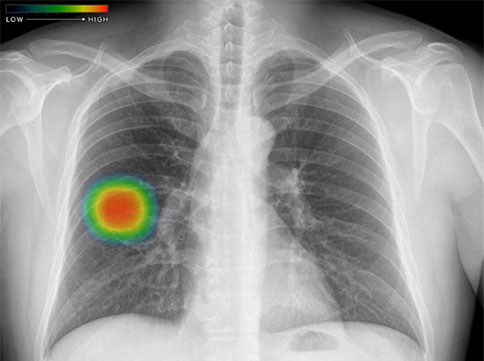

X線撮影装置 CLINIX3